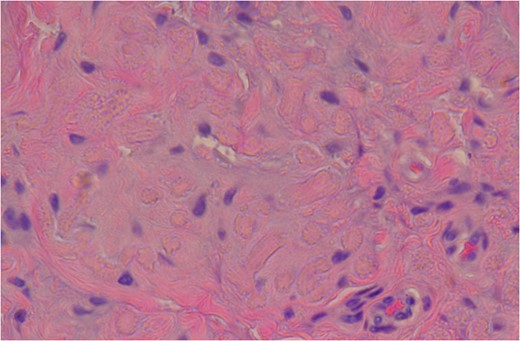

High Power slide showing elastic fibres (pink areas) which confirms the diagnosis of elastofibroma. (Altered elastic fibres in a collagenous matrix).

Histological sections show an admixture of alternating collagen bundles with abnormal elastic fibres. The elastic fibres have a degenerate fragmented appearance of petalloid globules or chenille bodies. The Verhoeff stain confirms these abnormal elastic fibres [9] (Fig. 9).

The Mason’s Trichrome stain also confirmed the diagnosis by identifying the elastic fibres by negative staining. The elastic fibres appear brown on the histological slides [9] (Fig. 10). MRI remains the diagnostic imaging modality of choice. It has the added advantage of detecting contralateral subclinical lesions which would clinch the diagnosis as in this case. A second issue is the left sided tumour which was not excised at the original surgery. The patient continues to remain asymptomatic on the left side and the tumour remains clinically impalpable. The patient has opted for conservative management of this lesion in the interim. There has been no increase in size to date and we have decided on serial imaging unless the patient becomes symptomatic.